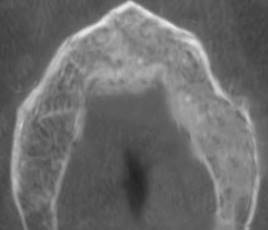

Se solicitó inicialmente radiografías periapicales de la zona afectada, donde se evidenció perdida de la continuidad del trabeculado óseo con zonas osteolítica irregulares, tenues y sin presencia de restos radiculares o cuerpos extraños (Fig.4 A, B). Para evaluar extensión de la lesión, se solicitó CBCT de maxilar, en el cual se observó un área radiolúcida y osteolítica localizada a nivel del tejido óseo maxilar, de 8,5 mm x 5,4 mm, de bordes irregulares, poco definidos, que no comprometían corticales vestibular, palatina, ni seno maxilar (Fig. 5). El estudio microscópico de los restos de tejido necrótico confirmó áreas de necrosis del tejido óseo con infiltrado inflamatorio, confirmando diagnóstico de ONM.